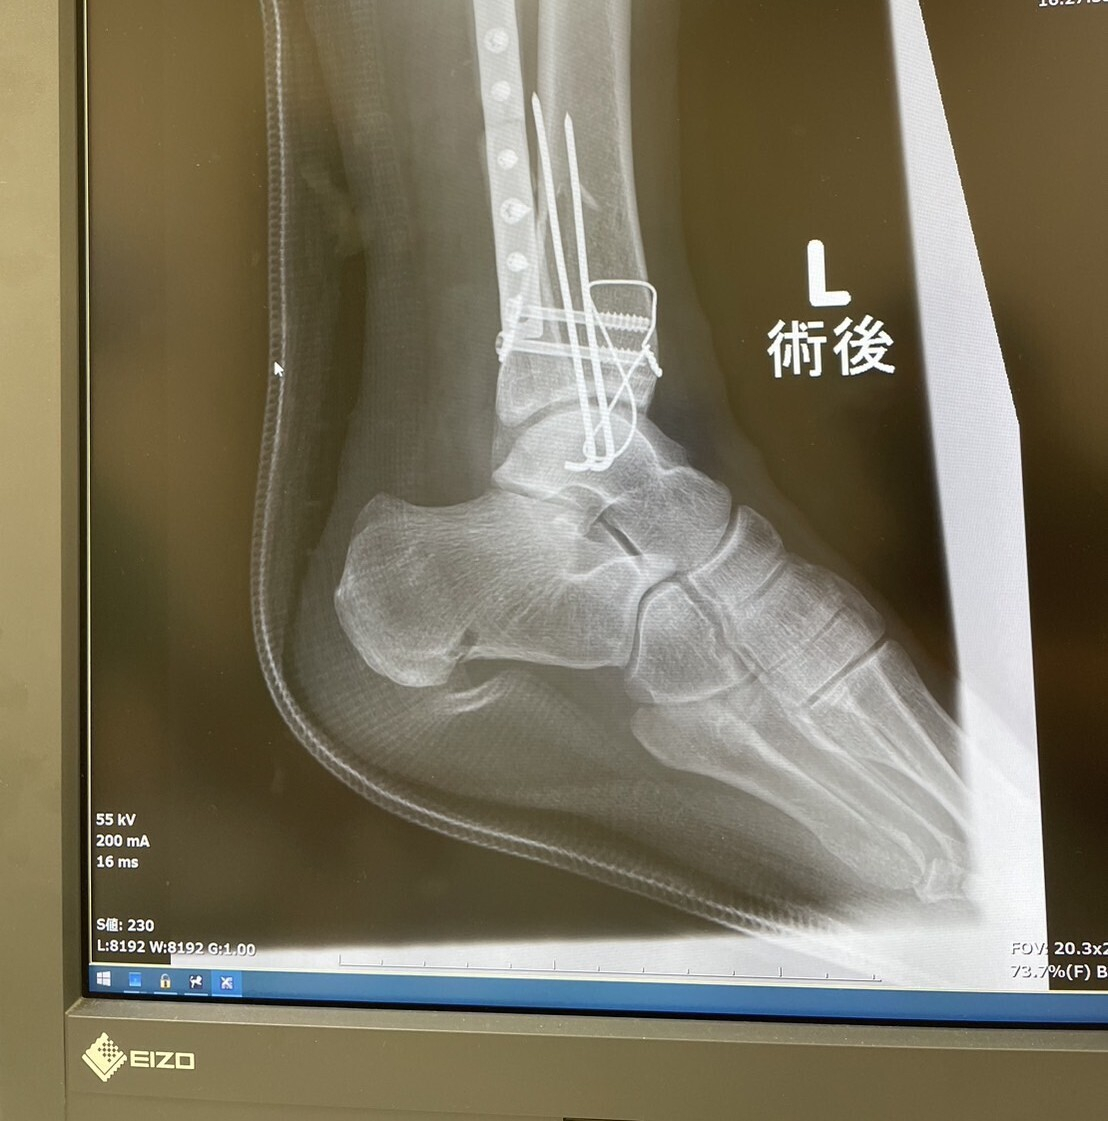

トップ > TORQUEフォト > 無事❓️に手術終了🥲 にしもん@50s pro 2024/08/16 17:41 無事❓️に手術終了🥲 予定の倍位の時間がかかりましたが、、、見事にサイボーグの様な足になって手術終わりました🥲💧 本人は麻酔が効いていて朦朧としているようです。 良く頑張った❗️❗️ TORQUE G06 サイボーグ いいね 共有する 共有する X facebook LINE リンクをコピー コメントする 9 件の返信 (新着順) ミュートしたユーザーの投稿です。 投稿を表示 ゐちこ 2024/08/17 08:56 当面はカルシウムのサプリメント接種せねばですね🫠 いいね 返信する ミュートしたユーザーの投稿です。 投稿を表示 にしもん@50s pro 2024/08/17 09:38 ゐちこ 今はどうかわかりませんが、骨折したらカルシウムの錠剤💊の様な薬を処方してくれました。ビタミンDだったかな😀❓️ いいね 返信する ミュートしたユーザーの投稿です。 投稿を表示 ゐちこ 2024/08/17 13:13 にしもん@50s pro 筋肉とかも関わって来るだろうしビタミンB12とかも必要かもですね🤔 いいね 返信する ミュートしたユーザーの投稿です。 投稿を表示 にしもん@50s pro 2024/08/17 13:21 ゐちこ 毎朝一緒にプロテイン生活が始まるかも知れませんね😅✨ まずは退院目指して貰います😀👍 いいね 返信する ミュートしたユーザーの投稿です。 投稿を表示 ささやん 2024/08/17 06:30 無事に終わって一安心ですね 色々と手続きやらも 続くと思いますが 頑張って下さい~ いいね 返信する ミュートしたユーザーの投稿です。 投稿を表示 にしもん@50s pro 2024/08/17 07:21 ささやん ありがとうございます😀☕ 今日から従業員が出勤してくるので身動き取りやすくなります💦 いいね 返信する ミュートしたユーザーの投稿です。 投稿を表示 You-g06 2024/08/17 05:32 おっとぉ~、すごい場所の手術されたんですね😰 無事に終わって良かったです😌 リハビリ大変でしょうけど頑張ってください🤗 いいね 返信する ミュートしたユーザーの投稿です。 投稿を表示 にしもん@50s pro 2024/08/17 07:22 You-g06 カルシウム補給メインで食事してもらおうかな😀☕💦 いいね 返信する ミュートしたユーザーの投稿です。 投稿を表示 You-g06 2024/08/17 07:59 にしもん@50s pro 骨を強化しないといけないですね💪 いいね 返信する ミュートしたユーザーの投稿です。 投稿を表示 ナナヨン 2024/08/16 21:52 大変な手術頑張られましたね。 いいね 返信する ミュートしたユーザーの投稿です。 投稿を表示 にしもん@50s pro 2024/08/16 22:06 ナナヨン 本人とはまだ連絡付きませんが、、、娘と妹さんから随時連絡が入るので手に取るように状況がわかりますね😀📳✨ いいね 返信する ミュートしたユーザーの投稿です。 投稿を表示 ran 2024/08/16 20:36 手術終わりましたね。 おめでとうございます。 明日以降の奥様が普通に歩ける用になることを願っています。 いいね 返信する ミュートしたユーザーの投稿です。 投稿を表示 にしもん@50s pro 2024/08/16 22:04 ran まだ歩くのは無理でしょう😅 いいね 返信する ミュートしたユーザーの投稿です。 投稿を表示 まぐろ大将 2024/08/16 20:05 手術は大変そうでしたね お疲れ様でした🥲 回復まで2,3年掛かりますが頑張って リハビリですね、お大事にしてください😭 いいね 返信する ミュートしたユーザーの投稿です。 投稿を表示 にしもん@50s pro 2024/08/16 20:17 まぐろ大将 記念品ですね😱💦やはりチタン😀⁉️ いいね 返信する ミュートしたユーザーの投稿です。 投稿を表示 まぐろ大将 2024/08/16 21:13 にしもん@50s pro たぶんチタン製です😀 相方も同じ様な部品を埋め込まれて いたサイボーグ人間です🦿🦾🤺 いいね 返信する ミュートしたユーザーの投稿です。 投稿を表示 たろ三郎@G07 2024/08/16 18:27 手術が無事に終わった様で良かったです。これからリハビリになるのでしょうか。早期の回復をお祈りします。 いいね 返信する ミュートしたユーザーの投稿です。 投稿を表示 にしもん@50s pro 2024/08/16 18:34 たろ三郎@G07 まずは思ったより入れたプレート❓️みたいなのが周りを壊死しないでくれたら早いらしいです😅💦なんせ遠いので、、、見舞いも行けてない🥲 向こうのお義父さんお義母さん怒ってるだろうな〜🥲💦 いいね 返信する ミュートしたユーザーの投稿です。 投稿を表示 きな☆彡 2024/08/16 17:57 にしもん@50s pro 無事に手術が成功する事が出来て良かったですね😅 私の場合は自然治癒力に頼って半年かかりましたけど手術が出来てキチッとした位置に折れた骨が付いたので治りは早いと思いますよ~✌️ これで一安心ですね😅 いいね 返信する ミュートしたユーザーの投稿です。 投稿を表示 にしもん@50s pro 2024/08/16 18:10 きな☆彡 予定では経過観察込で1ヶ月です🥲入院が、、、まぁ私も2ヶ月入院していたのでそのくらいはかかるかな、、、🥲 アイス食べちゃうぞー😀 いいね 返信する ミュートしたユーザーの投稿です。 投稿を表示 きな☆彡 2024/08/16 18:17 にしもん@50s pro 後は日にち薬ですね😅 今夜辺り一番しんどくて痛い😖💥と思いますけど明日ぐらいには元気になりますよ😃 後はお迎えとボルトの取り出し手術ですね😅 いいね 返信する ミュートしたユーザーの投稿です。 投稿を表示 にしもん@50s pro 2024/08/16 18:25 きな☆彡 今は数年後とかにする事もあるそうです😅🍺 まずは日常を取り戻したい、、、 入院長いと途中で支払いが発生するので、振り込みいけるのかな、、🥲 いいね 返信する ミュートしたユーザーの投稿です。 投稿を表示 きな☆彡 2024/08/16 18:40 にしもん@50s pro 健康保険高額療養費支給申請した方が良いですよ~✌️ 前妻ががんで入院して13時間の手術費用が恐ろしい金額でした~😱 社会保険適用で請求額が¥1,900,000でした~😱 病院の事務局に相談したらを高額医療を請求して下さいと言われて支払いしたら¥120,000でしたよ~✌️ レセプトの締切日が大体毎月10日と思われますのでそれまでに健康保険高額療養費支給申請して退院出来たら良いのですね~🫡 と同時に生命保険会社に申請書類をもらい退院時に事務局で記入して保険会社に送付し保険料支払いをした方が良いと思います。 宮城県と奈良県では離れ過ぎて時間がかかりますよ~✌️ https://www.kyoukaikenpo.or.jp/g2/cat230/r119/ いいね 返信する ミュートしたユーザーの投稿です。 投稿を表示 にしもん@50s pro 2024/08/16 19:01 きな☆彡 今はマイナンバーカードで高額医療請求は自動で受付でしてくれます😀✨ 保険会社は、、まだそこまで手が回って無いですね😅💦 いいね 返信する ミュートしたユーザーの投稿です。 投稿を表示 ドラえもん 2024/08/16 17:53 手術成功でひと安心ですね。 ☺️☺️☺️ この後のリハビリのサポート頑張ってください。 ☺️☺️☺️ 早く奥さんが戻ってこられる事を願ってます。 ☺️☺️☺️ いいね 返信する ミュートしたユーザーの投稿です。 投稿を表示 にしもん@50s pro 2024/08/16 18:13 ドラえもん 迎えに行く段取りも考えないと、、、😰 仕事のピークまでに何とか回収❓️したいです。 リハビリは、、、近場で探します😅 いいね 返信する TORQUE G06 2023年10月発売。TORQUE初の3眼カメラ搭載。29項目の耐久試験にクリアしつつ、小型・軽量化を実現。 詳細を見る